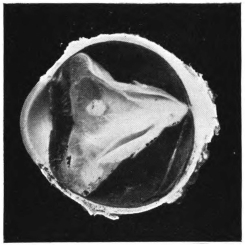

PLATE II.

FACING

PAGE

10.

LENS DISLOCATED BETWEEN CILIARY BODY AND SCLERA

curly bracket span

38

11.

NUCLEUS OF CATARACT FREELY MOVABLE BETWEEN THE AQUEOUS AND VITREOUS CHAMBERS

12.

LENS IMPACTED IN ANGLE OF ANTERIOR CHAMBER

13.

CAPSULE OF MORGAGNIAN CATARACT IMPACTED IN ANGLE OF ANTERIOR CHAMBER

14.

LENS FLOATING FREE IN VITREOUS CHAMBER

15.

LENS LIGHTLY IMPRISONED IN EXUDATE INTO VITREOUS CAVITY